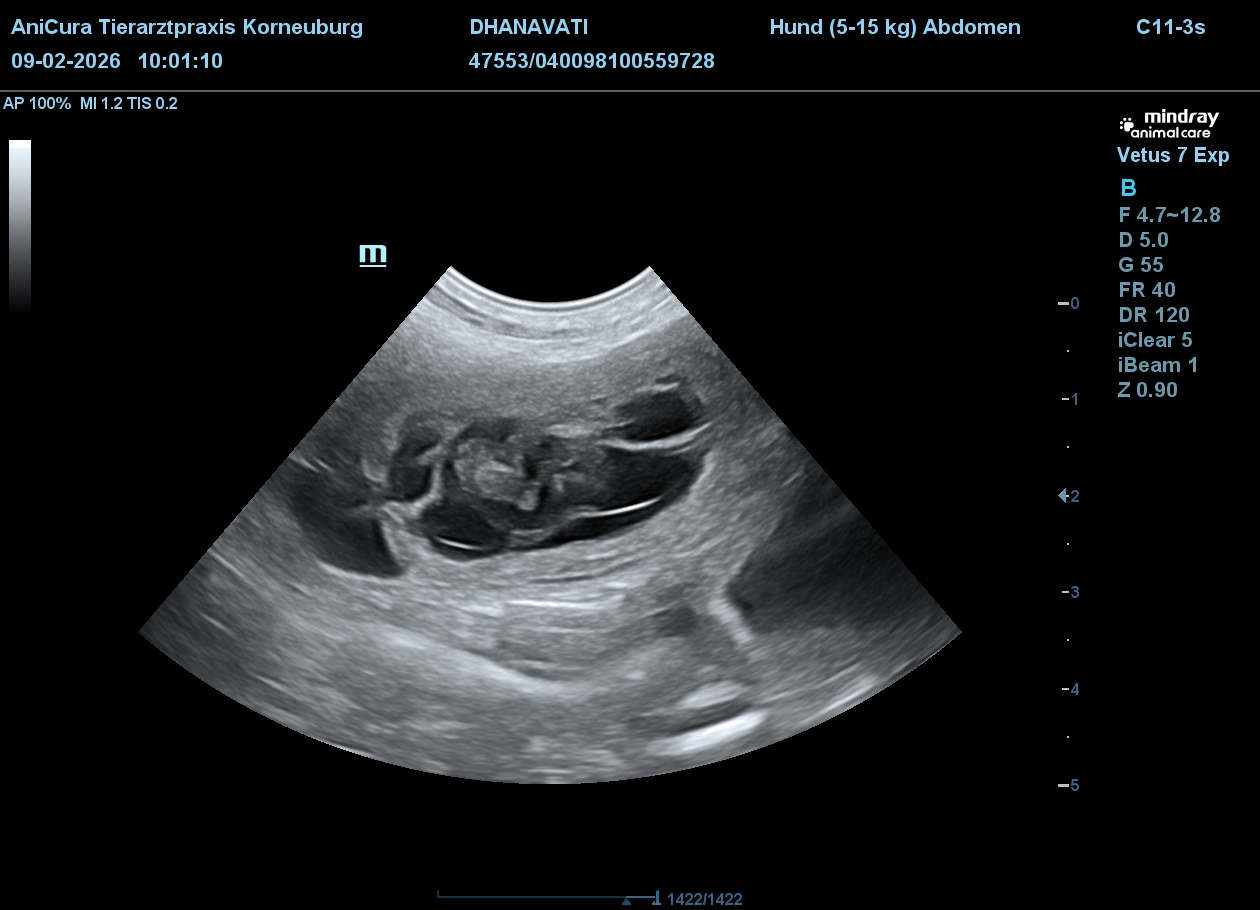

Es ist Anfang der 5. Woche, der 30. Tag. Die Ultraschalluntersuchung ist angesagt! Alle sind gespannt.

Der Ultraschall in der Tierklinik zeigt mehrere kleine Hundebabys. Man sieht deutlich Details. Die sehen zwar noch lange nicht nach einem fertigen Hund aus, aber man kann schon die schlagenden Herzen beobachten.